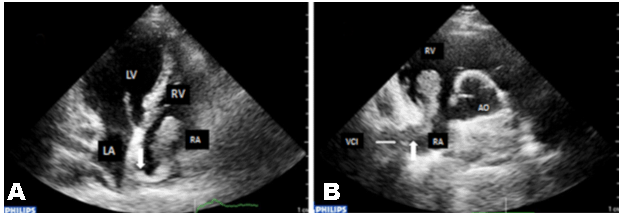

A 53-year-old female patient was admitted to our center because of dyspnea and chest pain. She had a previous history of diabetes mellitus (DM) and had orthotopic liver transplantation (OLT) six months back because of hepatitis B virus (HBV) infection. She presented with a three-week history of chest pain and progressive shortness of breath. Cardiac auscultation was unremarkable, body temperature was 37°C, blood pressure was 130/85 mmHg, heart rate was 85 beats per minute. Respiratory examination and electrocardiogram were normal. Laboratory tests pro-NT brain natriuretic peptide and D-dimer were normal. Lung scan excluded pulmonary embolism. The chest X-ray and computed tomography (CT) scan were normal. CT scan showed a 3.5x1.5x2.5 cm mass in the right atrium near IVC orifice. There was no evidence of deep vein thrombosis on duplex scanning and V/Q scan was negative. Echocardiography showed that the mobile right atrial mass was highly suspicious of a thrombus traversing the right atrial cavity during the cardiac cycle. It was accompanied with free-floating parts of the thrombi. It vertically stretched in the RA and during diastole touched the tricuspid valve (Figures 1A, B). 3DTTE was performed to further confirm the nature of mass. It showed a highly mobile homogenous thrombus, irregular in contour, measuring 3.9×1.8 cm, which originated from IVC and protruding into the RA cavity (Figure 2A). Patient was started on low molecular weight heparin and warfarin. Warfarin dose was adjusted to INR ratio 2–3. The patient had an uneventful hospital course and after one weeks, follow-up the thrombus began to shrink. After three weeks, echocardiography confirmed no evidence of residual thrombus (Figure 2B).

Figure 2: Mobile mass in the right atrium. A) 3DTEE shows a highly mobile thrombus, homogenous, irregular in contour, measuring 3.9×1.8 cm, arrow showing echo-lucent area, B) Follow up after three weeks of anticoagulation. Apical 4-chamber view TTE view shows complete disappearance of the thrombi. (LV = left ventricle; RA = right atrium; RV = right ventricle, LA=left atrium, IVC= inferior vena cava).